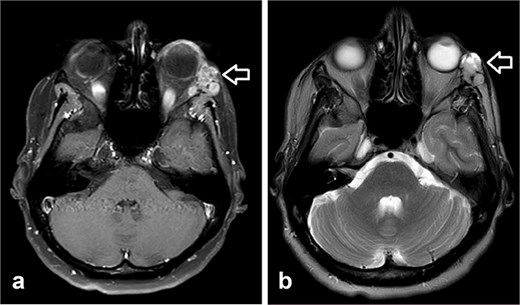

During follow-up, the patient complained of swelling at the left angle of the mandible and left lateral canthus. Orbit MRI showed local disease progression (Fig. 4). Ultrasonography of the left parotid region showed an irregular hypoechoic lesion in the left parotid gland. A PET scan revealed hypermetabolic malignant irregular soft tissue thickening within the lateral periorbital area of the left eye, consistent with a recurrence disease. Additionally, there is a new hypermetabolic irregular soft tissue mass in the left parotid gland with numerous bilateral scattered pulmonary nodules (Fig. 5). A biopsy from the left parotid gland confirmed the diagnosis of ACC, aligning with the primary tumor. The patient was diagnosed with lacrimal gland ACC with metastasis to the left parotid gland and the lungs. The Head and Neck multidisciplinary team proceeded with systemic chemotherapy using cisplatin and Navelbine. The patient started chemotherapy with good tolerance and clinical response and is now on regular follow-up with the oncology clinic.

Orbit MRI showed a lobulated, well-defined lesion, hyperintense to intermediate on T2W (b) and hypointense on T1W (a) structures with cystic changes, measuring 2.3 × 1.9 cm and 2.6 × 1.6 cm, compared with the previous study, the lesions have increased in size.